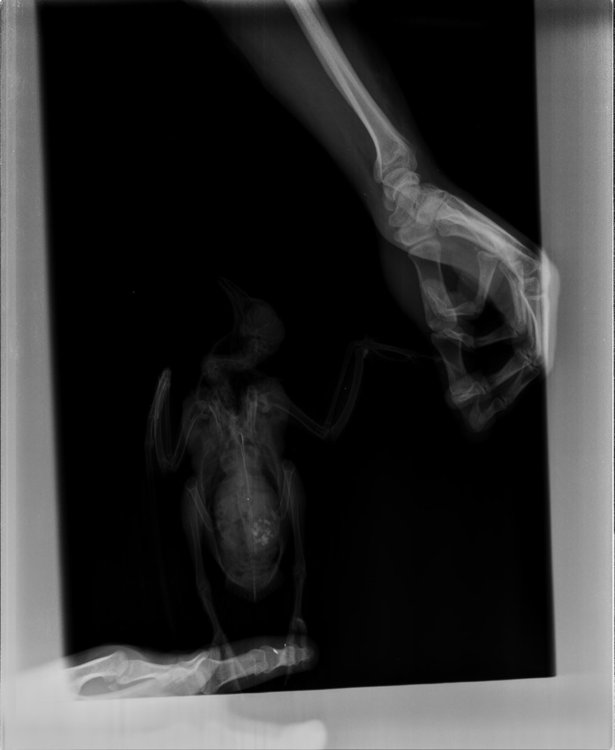

Duch Опубликовано 30 марта, 2020 #1 Опубликовано 30 марта, 2020 Здравствуйте! Приютился у нашего офиса, примерно 2 месяца назад, голубь и никак не улетал. Сделали вывод, что проблемы с крылом, т.к. левое он странно прижимал к себе. Положили в коробку, налили воды, насыпали гречи. Отогрелся спустя неделю, но крыло так и прижимал к себе. Предположили перелом крыла. Отвезли к орнитологу, сделали снимок (прикрепили к топику). Общий осмотр весьма позитивен, на снимке перелома нет. Выписали уколы витаминов и обезболивающих. Прокололи курс недели 2 назад - без изменений. На данный момент крыло так и прижимает к себе, огрызается, когда ему сыпят корм или доливают воды. Иногда клюёт и бьёт крылом, но только правым. Пока ждём выхода орнитолога из очередного отпуска, стараемся за ним ухаживать. В прошлую пятницу насыпали ему корм и подлили воды в плошку. Приехал в субботу вечером, дабы проведать. В итоге, он за целый день ничего не съел и не пил. На мои касания никак не реагировал: вжался в себя и стоял напуганный. Взял на руки, дабы осмотреть, как из под него показалась муха/слепень и тут же скрылась. Погуглил - оказывается, это - кровососки. Купил в ветеринарном отделе ампулу с препаратом, которую следовало разбавить 1,6л воды. Опрыскал её под крыльями, напоил водой из шприца и оставил так на день. Судя по корму, начал немного есть и пить. Кормплю гречкой, рисом и разваренным пшеном из шприца. Но сегодня обратил внимание, что он, когда клюёт сухой корм, как бы, промахивается и не может заглотить крупинку - гречка отскакивает в сторону и пытается еще раз захватить другую, но результат тот же. При всем при это, он четко видит мою руку и реагирует на неё соответствующим образом, т.е. слепоты нет Очень рассчитываю на вашу помощь! Ранее не имел опыта ухода за птицами

Виктория М. Опубликовано 30 марта, 2020 #2 Опубликовано 30 марта, 2020 (изменено) Здравствуйте. Нужен точный вес голубя. Помет желательно на листе белой бумаги. Проверьте нет ли наростов во рту , а также неприятныого запаха (кислого, тухлого). Кормить; 1 столовая ложка с горочкой 2 раза в день. Помимо гречи добавьте перловую крупу ,чечевицу или колотый горошек, пшеницу, овес без шелухи. Рис лучше уберите его можно но совсем немного. С каким препаратом ампула была? Все что обнаружил врач и все его назначения нужно выложить сюда на сайт, чтобы понимать чем вы лечили птицу. Какие витамины кололи какой курс и тд. Чтобы голубь начал нормально клевать зерно, в человеческой аптеке купите ноотропил таб или пирацетам . В вет аптеке нужно приобрести Фоспренил. Мух кровососок если вдруг еще обнаружите хорошо в тазике с водой вылавливать. Сажаете птицу в тазик с теплой водой, чтобы только голова на поверхности была, придерживаете аккуратно и так мин 10 -15 сидите с ним они начнут всплывать. Ваша задача не дать им вылететь из воды - передавить. Какое крыло он прижимает если смотреть на ренген? Изменено 30 марта, 2020 пользователем Виктория М.

маленький принц Опубликовано 1 апреля, 2020 #5 Опубликовано 1 апреля, 2020 (изменено) а можно рентген более крупный а не мелкий? у Вас на этой мелкой картинке трудно разглядеть подробности ВНОВЬ ЛЕТАТЬ и Здоровья Вашему голубю! чтобы узнавать новые ответы в Вашей теме нажмите пожалуйста наверху Вашей темы "подписаться" Изменено 1 апреля, 2020 пользователем маленький принц

Duch Опубликовано 1 апреля, 2020 Автор #6 Опубликовано 1 апреля, 2020 31.03.2020 в 01:36, Виктория М. сказал: Здравствуйте. Нужен точный вес голубя. Помет желательно на листе белой бумаги. Проверьте нет ли наростов во рту , а также неприятныого запаха (кислого, тухлого). Кормить; 1 столовая ложка с горочкой 2 раза в день. Помимо гречи добавьте перловую крупу ,чечевицу или колотый горошек, пшеницу, овес без шелухи. Рис лучше уберите его можно но совсем немного. С каким препаратом ампула была? Все что обнаружил врач и все его назначения нужно выложить сюда на сайт, чтобы понимать чем вы лечили птицу. Какие витамины кололи какой курс и тд. Чтобы голубь начал нормально клевать зерно, в человеческой аптеке купите ноотропил таб или пирацетам . В вет аптеке нужно приобрести Фоспренил. Мух кровососок если вдруг еще обнаружите хорошо в тазике с водой вылавливать. Сажаете птицу в тазик с теплой водой, чтобы только голова на поверхности была, придерживаете аккуратно и так мин 10 -15 сидите с ним они начнут всплывать. Ваша задача не дать им вылететь из воды - передавить. Какое крыло он прижимает если смотреть на ренген? Прикрепил назначение врача Во рту ничего подозрительного, как и в запахе. Может прозвучать неоднозначно, но он в вцелом, приятно пахнет) Ампула, которую разбавил в воде и опрыскивал 2 дня голубя под перья ( на тело) - "Дельцид" В воду окунали, правда держали минут 5. Ничего не всплыло и мы аккуратно его сушили феном, т.к. он сильно замёрз. Потом на форуме прочел, что насильное купание голубей недопустимо Глядя на рентген то, что раскрыто, т.е. правое. Делали снимок лёжа на спине, соответственно, по факту, это левое крыло

OFA Опубликовано 2 апреля, 2020 #25 Опубликовано 2 апреля, 2020 @Duch сама доктор смотрела рентген птицы? Что-то сказала? Нужно позвать нашего форумского доктора @Zosia посмотреть рентген. Может так разложена птица, но мне что-то кажется, что плечевой сустав не в порядке, но лучше пусть Зося посмотрит. Птица взрослая, клевать умеет, значит проблема или с жкт, или вертячка в такой форме.

маленький принц Опубликовано 2 апреля, 2020 #26 Опубликовано 2 апреля, 2020 @OFA рентген - в виде мелкой картинки просил автора залить рентген покрупнее

маленький принц Опубликовано 2 апреля, 2020 #30 Опубликовано 2 апреля, 2020 (изменено) @Duch вот рентген Вашего пациента Изменено 2 апреля, 2020 пользователем маленький принц

маленький принц Опубликовано 3 апреля, 2020 #33 Опубликовано 3 апреля, 2020 12 часов назад, Duch сказал: ну да, разве не его я прикрепил в прошлом сообщении? оно почему-то ужалось до мелких размеров если пойти по ссылке https://www.mybirds.ru/forums/uploads/monthly_2020_03/1SXcxYu_0rk.jpg.d7c82758490ddb04a65127b887286e57.jpg.28c0e1b9697a84b0cce71b1ee39e8254.jpg и открыть то видно что оно очень мелкое потому я скачав Ваш архив перезалил фото и увидев что оно ограничено по размерам дважды обрезав перезалил ещё раз